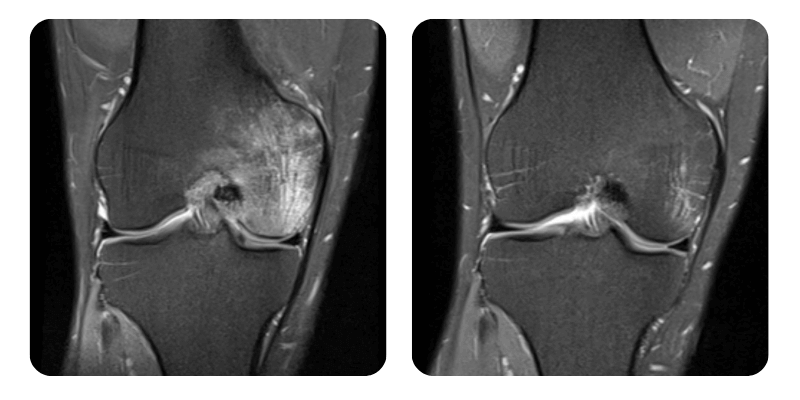

Prima

Dopo

M.I.V., 39 anni - Edema osseo del condilo femorale esterno del ginocchio destro

Diagnosi: Edema osseo del condilo femorale esterno del ginocchio destro.

Dopo 20 sedute di ossigenoterapia iperbarica si osserva una remissione dell'edema di circa il 70%. Si raccomanda la prosecuzione del trattamento con altre 20 sedute.